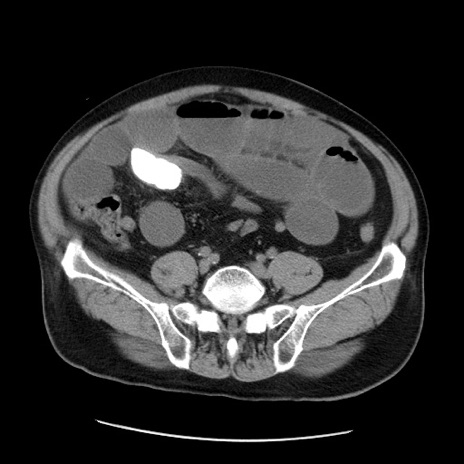

症例20(横断像)

【症例】 60歳代男性

【主訴】 腹部膨満、嘔吐

【現病歴】5日前頃より倦怠感を認め食事量減少し4日前の朝嘔吐、食事摂取困難となった。 3日前近医受診し点滴施行され整腸剤などを処方された。 当日他院を受診し、腹部膨満著明、炎症反応の上昇(CRP10.8、WBC11200)あり、紹介受診となる。

【身体所見】 意識JCS1 受け答えがはっきりしないBP 111/57mHg、 P 67bpm、、BT35.2°C、SpO2 97%(RA)、 腹部:膨隆、打診で鼓音あり、全体的に圧痛有り、腸蠕動音(-)、反跳痛ははっきりせず。

【データ】WBC 11400、CRP 14.20